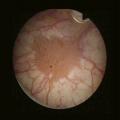

Urétro-cystoscopie

L’urétro-cystocopie, ou fibroscopie vésicale, permet l’exploration endoscopique de la vessie (fig. 3). Elle est réalisée en consultation sous anesthésie locale, après vérification de la stérilité des urines et permet de confirmer la présence d’une tumeur de vessie mais aussi de préciser le nombre, la taille, la topographie et l’aspect de la tumeur (papillaire, sessile, ou plage érythémateuse en cas de carcinome in situ). Elle permet aussi d’éliminer les diagnostics différentiels de tumeur vésicale en échographie, notamment l’existence d’un caillot sanguin intra-vésical.